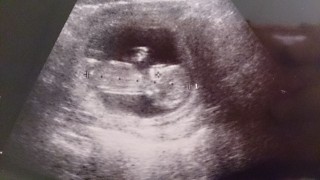

はっきりと手足が確認出来たので安心しました。

背骨が見えます。前回(9w)の時はよく見えなかったけど、人間らしくなり、より実感がわいてきました。

順調に育ってくれてて良かったぁ♪